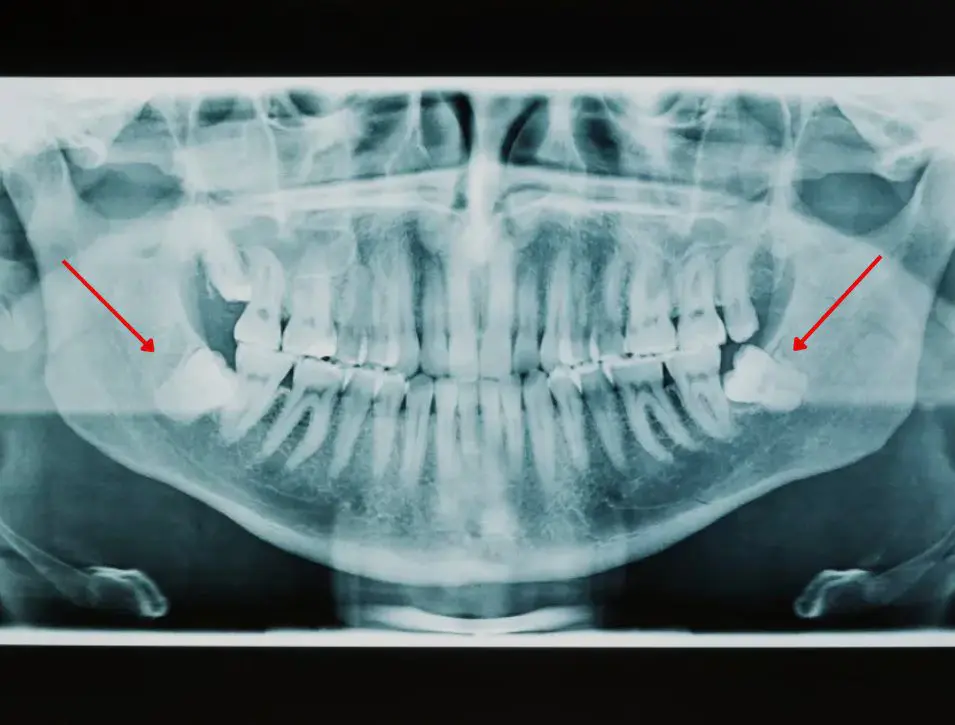

Panorex X-ray

Also known as a panoramic X-ray, is a special type of dental imaging that provides a wide, 180-degree view of your entire mouth, including your teeth, jaw, and surrounding structures. Unlike traditional X-rays that focus on individual teeth, a Panorex captures an image of your whole mouth in one shot.

Panorex X-ray Before OP / After OP